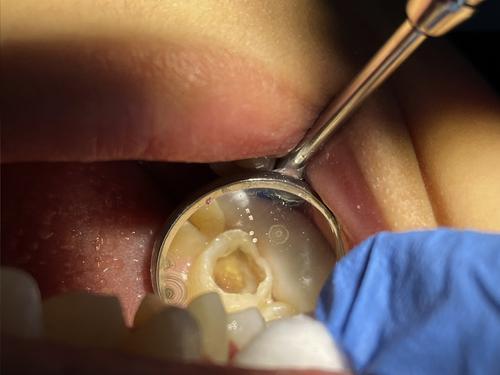

这名4岁男童在东姑阿都拉曼路后巷寻找牙科服务,目睹男童的牙齿状况,令在场的牙医深感悲痛,因为男童的乳牙几乎已脱落,残留的10多颗牙齿面临无法挽回的蛀牙问题。

为了挽救这名男童的牙齿健康,牙医无可奈何下作出艰难决定,拔掉了男童的所有乳牙。他们深知,这是为了防止牙龈或牙根严重发炎,避免潜在的并发症,例如牙龈肿胀、生脓和敏感等。

DFTN@Chow Kit秘书兼马来西亚理科大学医院牙科公共卫生专科讲师莫哈末纳兹米接受马新社访问时说:“这名男童患有严重的早期儿童龋齿,我们不得不提前拔掉他所有牙齿。在恒齿长出来之前,每颗乳牙都会自动脱落,例如门牙在6至7岁时脱落,这取决于牙齿结构。

“如果在恒齿长出来之前,这些乳牙提早2、3年脱落,这些孩子就会面对进食困难,从而影响牙的生长发育,因为缺乏足够营养。”